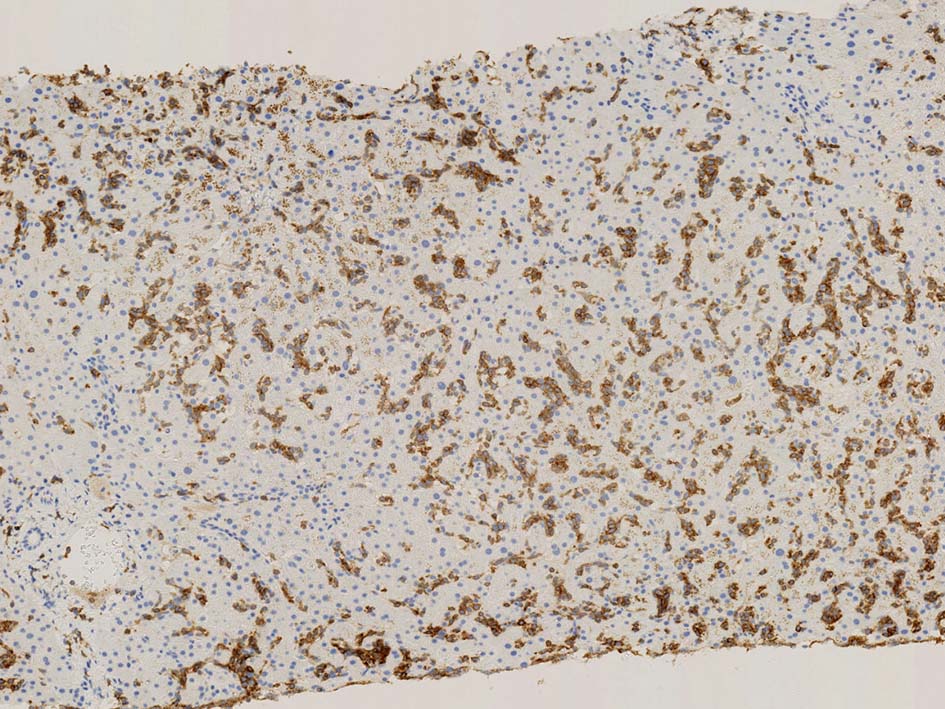

類洞内で増殖する腫瘍細胞はCD3+, CD7+のT-cellであるがCD5発現が弱く, 異常なT-cellである.

CD4は類洞内皮/macrophageの一部が陽性であるが, 類洞内腫瘍細胞の多くは陰性を示す(陽性と間違えないこと). CD8陰性. CD20陽性リンパ球はごく少ない.

TIA1は陽性であるが, granzymeBは陰性細胞が多い.

ASD-GiemsaではASDに染まらない(陰性の)あやしい細胞塊があるように見える. 細胞小塊はCD3陽性.

骨髄クロットでは, 十分量が採取されているにもかかわらず, CD3陽性細胞は微小な集簇巣が2個ほど認められるのみであとは散在している.

免疫染色でCD3陽性となる細胞集塊のASD-Giemsa像. 肝類洞内浸潤細胞に比較して核, 細胞が紡錘形の傾向を示している.